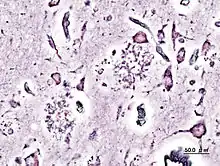

La pratique de la neuropathologie moderne repose essentiellement sur l'examen au microscope de spécimens de tissus nerveux prélevés chirurgicalement chez un patient : il peut s'agir de biopsies cérébrales ou de lésions médullaires détectées par les techniques d'imagerie médicale. Il peut aussi s'agir de biopsies de nerfs périphériques ou de biopsies musculaires. Plus rarement qu'au XIXe siècle, la neuropathologie peut encore avoir recours à l'autopsie pour établir un diagnostic post-mortem.

Les échantillons prélevés sont fixés et inclus dans des blocs de paraffine, puis coupés en fines lamelles au microtome.On utilise largement en première intention les colorations simples comme celles à l'hématoxyline-éosine (HE). Lorsqu'un diagnostic rapide est nécessaire, par exemple au cours d'une intervention chirurgicale sur une tumeur (diagnostic extemporané), les fragments prélevés par le neurochirurgien sont congelés et découpés à l'aide d'un cryotome. On a largement recours aux techniques d'immunofluorescence directe qui utilisent des anticorps dirigés contre différents antigènes tumoraux.

La neuropathologie utilise traditionnellement l'imprégnation métallique pour visualiser les cellules nerveuses en microscopie optique. Les techniques d'imprégnation argentique selon Golgi ou del Río Hortega se sont avérées particulièrement précises.